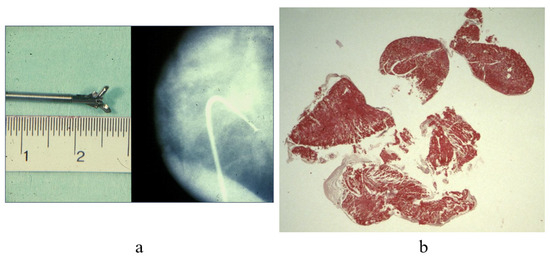

7. Clinical Indications of Endomyocardial Biopsy

- Poletti, A.; Cocco, P.; Valente, M.; Fasoli, G.; Chioin, R.; Thiene, G. In Vivo Diagnosis of Cardiac Angiosarcoma by Endomyocardial Biopsy. Cardiovasc. Pathol. 1993, 2, 89–91. [Google Scholar] [CrossRef]

- Basso, C.; Stefani, A.; Calabrese, F.; Fasoli, G.; Valente, M. Primary Right Atrial Fibrosarcoma Diagnosed by Endocardial Biopsy. Am. Heart J. 1996, 131, 399–402. [Google Scholar] [CrossRef] [PubMed]